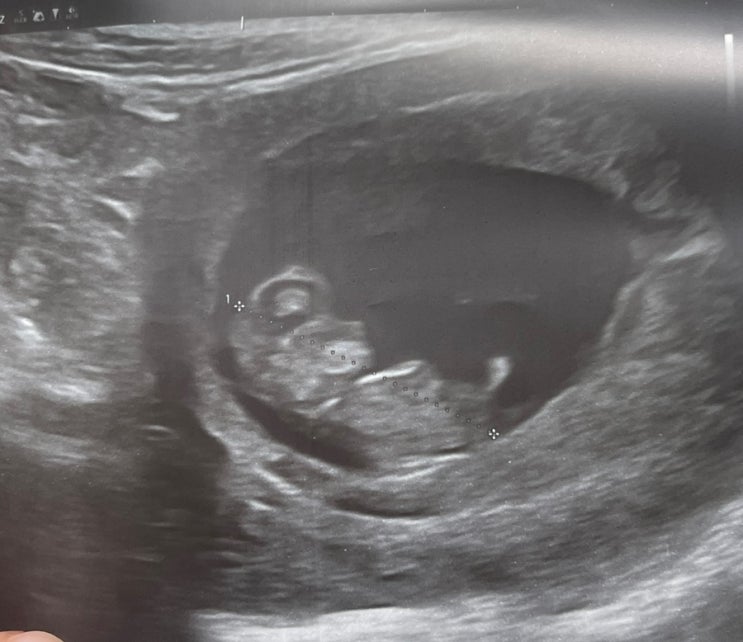

10주~11주 드디어 배 초음파, 하이베베 성공

남편과 급 정선 1박2일 여행에 다녀왔다. 행복이 10주 진입 기념겸 남편 회사 휴무에 맞춰서 다녀온 여행. ...